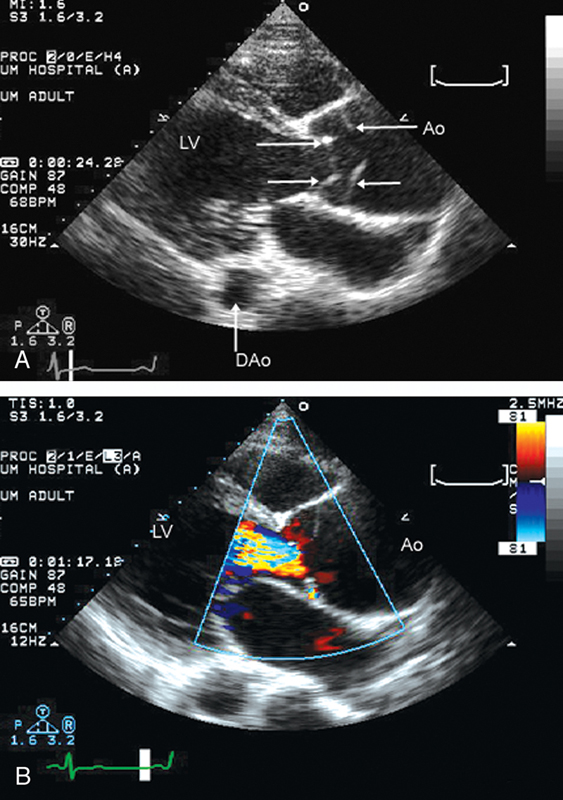

فحوصات تشخيصية لبعض امراض القلب والشرايين التاجية